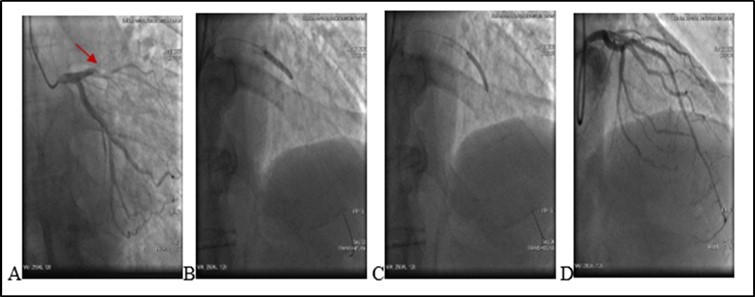

After angioplasty two weeks later (20.06.2020) 13:25 Pm the patient presented severe chest pain and he was readmited again in the same institution with diagnosis: Coronary artery disease. ST segment elevation MI. Arterial Hypertension I (ESH/ESC). Coronary artery stenting . (LAD 1 Bare Metal Stent (BMS) 08.06.2020).

On ECG : HR 78 . Sinus rythm. ST segment elevation I, aVL, V1- V5 (2mm at the J-point). Q wave in V2-V4 leads. T/A 180/70 mm Hg. Patient refused missing of presribed medications. Due to severe chest pain, ECG data and haemodynamic instability an urgent PCI was performed. It revealed a stent thrombosis in LAD - early stent thombosis (1). Circumflex Coronary artery (CX) and Right Coronary artery (RCA)- without significant changes (see Figure 2).

Figure 2.(20.06.2020) .A. Occluded stent due to early thrombosis (red arrow). B.C Balloon angioplasty and stenting. D. Final result.

After administration of a 180 mg loading dose of ticagrelor and an intravenous bolus of 10.000 units heparin, left main coronary artery was cannulated with a 6F EXB4 guiding catheter and a 0.014’’ floppy guide wire was advanced in LAD. Coronary artery recanalisation performed successfully. After baloon angioplasty with 3.0X12 mm baloon-catheter, in proximal and medial segments intraluminal filling defect was observed – reduced contrast dencity and heziness and two BMS were overlaped - 3.5X24 mm and 3.0X24 mm respectively. Postdilation was performed at the end of the procedure.TIMI score was 3. Procedure performed without any techincal complication during coronary intervention. Patient was stable and he was transferred to the Intensive Care Unit.